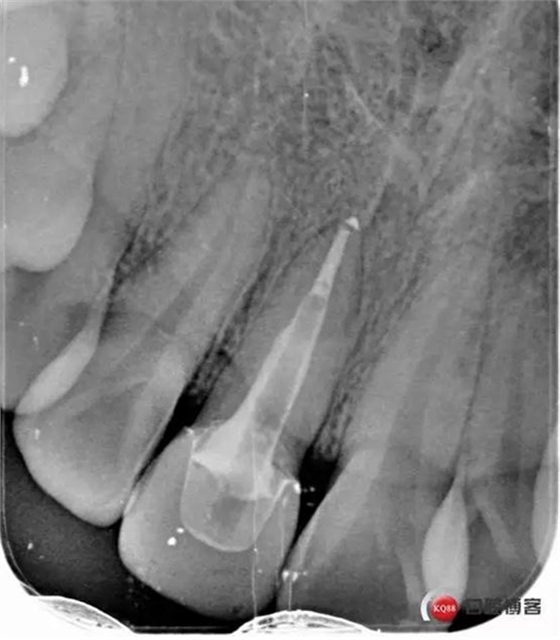

看起來有點(diǎn)頭痛哈,拍片檢查

牙根長(zhǎng)度比較號(hào),根充完善。這張片子也可以看出,為什么上次脫落了,樁的深度不夠,而且明顯樁根樁道不匹配,打的樁都沒有到位。

術(shù)后牙片可以看出樁的長(zhǎng)度有明顯增加。到達(dá)預(yù)備長(zhǎng)度。術(shù)后齦緣高度與鄰牙一致